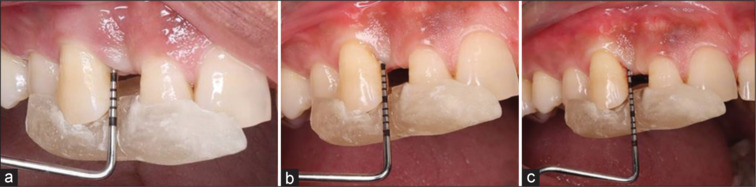

牙周骨缺损是牙科学的一大挑战,需要有效的治疗策略。本病例报告探讨了用提取牙齿的颗粒牙本质移植物(PDG)和重组人血小板衍生生长因子(rhPDGF)作为骨移植材料治疗人牙周下颌骨缺损的再生潜力。一名44岁男性患者表现为9 mm的牙袋探查深度(PPD)和8 mm的骨下缺损深度(近13 #),无牙龈退缩(GR)。在I期治疗后,进行开放皮瓣清创和PDG和rhPDGF移植。在基线、6个月和12个月进行临床和影像学测量。12个月时,观察到PPD减少6mm,临床附着水平增加,无GR。x线片显示5 mm(83.33%)骨填充。在本病例报告的限制下,利用PDG与rhPDGF治疗骨下牙周缺损已成为一种有前途的再生疗法。

Periodontal bone defects pose significant challenges in dentistry, necessitating effective treatment strategies. This case report explores the regenerative potential of using a combination of particulate dentin graft (PDG) derived from extracted teeth and recombinant human platelet-derived growth factor (rhPDGF) as bone graft material for the treatment of human periodontal infrabony defects. A 44-year-old male patient presented with a 9 mm pocket probing depth (PPD) and an 8 mm infrabony defect depth mesial to #13, with no gingival recession (GR). Following Phase I therapy, open flap debridement and grafting with PDG and rhPDGF were performed. Clinical and radiographic measurements were taken at baseline and 6 and 12 months. At 12 months, a 6 mm reduction in PPD and clinical attachment level gain were observed with no GR. 5 mm (83.33%) bone fill was seen radiographically. Within the limitations of this case report, the utilization of PDG with rhPDGF for the treatment of infrabony periodontal defects has emerged as a promising regenerative therapy.